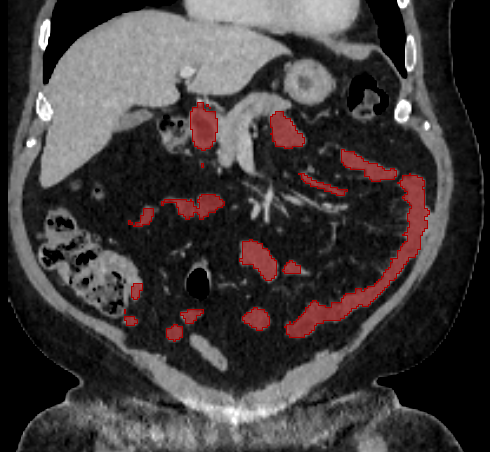

Over the years, there have been attempts to develop automatic methods for small bowel segmentation, especially using deep learning. The small bowel was included in segmenting multiple organs-at-risk for radiotherapy treatment planning of affected tissues, such as pancreatic and cervical cancers, in CT scans [8, 9, 13]. Although the results obtained for the small bowel are reasonable, some of their data included only the part of the small bowel that is closest to the target area, which needed to be dose-evaluated [8, 9]. In [13], the rough bowel location was detected instead of performing pixel-accurate small bowel segmentation. There have been only a few previous works dedicated solely to automatic small bowel segmentation [12, 14, 21]. While the specific anatomic relationship between the mesenteric vasculature and the small bowel is used to guide the small bowel segmentation in [21], a cylindrical shape constraint is applied during training of the small bowel segmenter in [14]. Although each of the works showed reasonable performance for particular datasets, their generalizability across different datasets was not evaluated. A CT scan is acquired using a specific imaging protocol depending on the purpose of the investigation, which includes the use of different contrast media and scan timing. Thus, the appearance of the small bowel may be different across datasets as exemplified in Figure 1. It is observed in our experiment that, when trained on one dataset, the model does not generalize well to another dataset due to the domain shift (section 3).

In this paper, we present a novel unsupervised domain adaptation method for small bowel segmentation, which is based on feature disentanglement. Although the absolute intensity values in CT scans (Hounsfield units) carry important information on specific substances of the human body, thus could provide a clue of being specific tissues and organs, they may be variable according to the imaging protocol. Figure 1 shows example CT scans that were acquired with and without oral contrast administration. The absolute intensity values are no longer a strong clue for the small bowel when we train and test across the datasets. Non-intensity features like texture and shape may be more useful. For example, local textures of the valvulae conniventes, which are circular folds on the inner surface of the small bowel, are more recurrent across the datasets.

3.2 Qualitative Evaluation

Figure 3 shows example segmentation results in 3D. The result corresponding to ‘feat. & out. level DA’ in Table 1 is compared to ours. We note that the only difference between them is whether the feature disentanglement is involved for the domain adaptation, thus could show its effectiveness. Fewer errors are observed for the proposed method. We believe this is because the proposed method explicitly concentrates on the features more transferable across the datasets, the non-intensity features in this work, by disentangling those features and applying adversarial learning directly to them during the adaptation process. Example reconstruction results from the auto-encoding architecture as well as segmentation results in coronal view can be found in supplementary material.